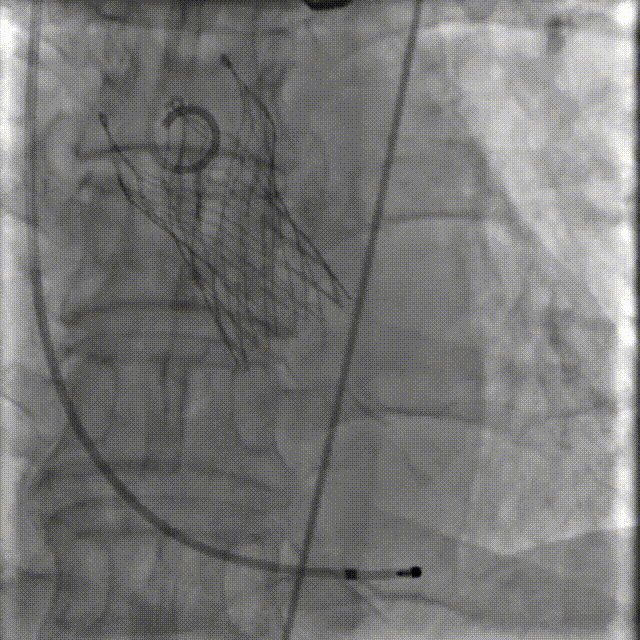

李有金教授 宁夏回族自治区人民医院 “随着人口老龄化加剧,主动脉瓣狭窄患者数量逐年增多,其中高龄、合并多种基础疾病的复杂病例占比不断提升。经导管主动脉瓣置换术(TAVR)作为微创治疗技术,已成为此类患者的重要治疗选择。对于高龄、有恶性肿瘤病史的患者而言,手术的安全性、微创性与长期疗效同等重要,既要最大程度降低手术创伤与并发症风险,也要确保瓣膜的耐用性与患者术后生活质量。 全球首款预装干瓣ProStyle A®的临床应用,为复杂病例治疗提供了全新解决方案。该瓣膜无需术中戊二醛冲洗,大幅缩短了手术操作时间,尤其适合高龄、心功能欠佳的患者。其独特的抗钙化工艺与优化的瓣架设计,既保证了瓣膜的长期耐久性,又能有效规避冠脉风险,为患者的“全生命周期管理”奠定了坚实基础。” 病例简介 现病史:患者半月余前突发抬头时一过性头晕,持续数秒钟,每日发作3-5 次,伴天旋地转感,症状可自行缓解。2025年12月12日就诊于外医院,心脏彩超提示“主动脉瓣狭窄(重度)并关闭不全(轻度),左室壁增厚,升主动脉增宽,左心室收缩功能正常,舒张功能减退”,建议转上级医院诊治。为求进一步治疗,患者就诊我院,门诊以“主动脉瓣狭窄”收住入院。 既往史:胃癌,胃大部切除术后五年。 临床诊断:“1.主动脉瓣狭窄伴有关闭不全(重度狭窄伴轻度关闭不全);2.主动脉瓣钙化;3.肥厚性非梗阻性心肌病;4.心功能不全;心功能III级(NYHA分级);5.升主动脉扩张;6.胃恶性肿瘤个人史” 术前CT评估显示:Type-1型二叶瓣,R-N钙化粘连,瓣叶重度钙化,主要分布在无冠窦瓣叶游离缘、R-N对合缘粘连处及右冠窦基底部;钙化积分933.2mm³;主动脉瓣环直径26mm,LVOT 27.6mm;双侧瓣叶开口高度可,左冠开口高度22.0mm,右冠开口高度20.0mm;主动脉水平夹角57.7°,左室内径偏小;主动脉弓部75.1°锐角弓;外周入路无明显迂曲及钙化,双侧股动脉内径可,右股中分叉。 手术策略 右侧股动脉为主入路,左侧为辅助入路,20F大鞘,股骨头中段穿刺;预装金仕生物 ProStyle A® AV26瓣膜,备29瓣膜,22mm球囊预扩;初始定位对齐瓣环上5mm超高位释放,释放过程中使瓣膜自然下滑至工作位,最终理想位置零位,利用瓣上锚定与封堵,规避冠脉风险;术前适当补液; 手术过程 Step1:主动脉根部造影; 主动脉根部造影 Step2:使用“先瑞达”22mm球囊预扩,无腰无漏,冠脉充盈良好; 球囊预扩 Step3:将ProStyle A®预装干瓣送至目标位置,初始定位后缓慢释放,观察瓣膜自然下滑至理想工作位; 定位 释放至工作位观察 Step5:瓣膜完全释放后,再次造影,显示瓣膜位置、形态良好,导管测平均跨瓣压差由术前60mmHg-降至1mmHg,冠脉血供正常; 最终造影 Step6:术后即刻超声监测,人工瓣膜位置固定,瓣叶启闭无受限,瓣周少量反流。 术后患者病情稳定,已于一周后出院。 结语 作为宁夏回族自治区心血管疾病诊疗的核心高地与区域医疗中心建设的标杆单位,宁夏回族自治区人民医院始终坚守“敬佑生命、救死扶伤”的医者初心,以“技术引领、学科兴院”为发展理念,在心脏大血管领域持续深耕,构建了集“精准评估-个性化方案-微创治疗-全程康复”于一体的诊疗体系。此次西北首例ProStyle A®预装干瓣植入手术的圆满成功,不仅是医院在复杂结构性心脏病介入治疗领域的又一突破性成果,更彰显了医院在引进前沿技术、转化创新器械、服务复杂重症患者方面的责任与担当。 Prostyle A®预装干瓣——助力临床最优化解决方案: 预装干瓣 便捷顺安:金仕生物专利抗钙化技术运用纳米技术去除组织内的细胞碎片和磷脂,封闭游离醛基,从根本上阻断了瓣膜钙化的多项因素,显著提升了瓣膜的耐久性;同时,相比较传统戊二醛保存方式,干式存储最大限度的保留心包的亲水亲油平衡,还原组织天然曲柔性,进一步保障了瓣叶开合,保证长期耐久性; 平衡径向支撑力:Prostyle A®瓣架网孔比例按照病例解剖结构的特殊设计,使瓣膜在狭窄最重的地方良好的撑开,同时避免对瓣环及周边组织的过度压迫,有效降低传导阻滞风险; 精准释放:底部桶状设计更易迅速锚定,协同释放张力小,助力最终精准释放; 过弓柔顺:较细的输送系统直径+亲水涂层,显著提升输送系统通过性,有效减少血管并发症的发生,内连鞘版本最小尺寸等效14F大鞘; 专家简介 李有金 宁夏回族自治区人民医院(点击查看专家详细简历) · END ·